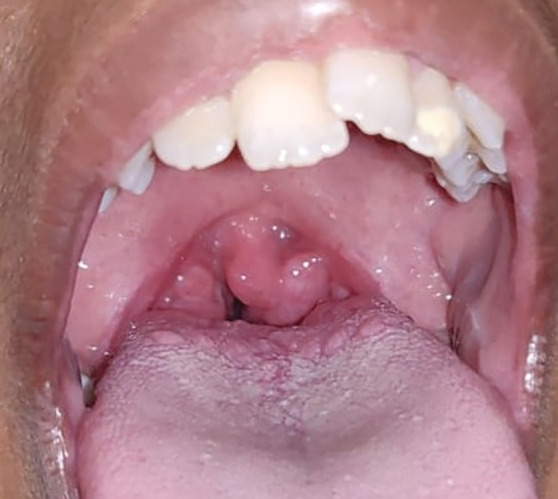

Materials and methods: This cross-sectional study was conducted on a total of 78 participants, aged 4-12 years, with 52 children with adenoid/tonsillar hypertrophy (group I) and 26 healthy children (group II). For each participant, a detailed history of respiratory obstruction or infection was recorded, followed by an orthodontic evaluation. A lateral cephalogram was taken for airway space and cephalometric analysis. Descriptive and inferential statistical tests were computed using SPSS software version 21.

Results: Children with hypertrophic adenoids and tonsils showed a higher incidence of repeated tonsillitis (73.07%) and otitis media (17.3%). On assessing breathing patterns, 88.4% had the mouth breathing habit and 11.5% had the oronasal breathing habit. However, the difference was not statistically significant (p > 0.05). On intergroup comparison, there was a statistically significant difference observed in cephalometric and orthodontic parameters. A higher frequency of lip incompetency, constricted maxillary arch, class II molar relationship, and the posterior crossbite was observed in children with adenotonsillar hypertrophy. Children in group I reported increased overjet (4.9 ± 2.0), increased mandibular plane angle (28.8 ± 3.1), and decreased posterior facial height (61.8 ± 6.1) with a dolichofacial profile (p < 0.05).